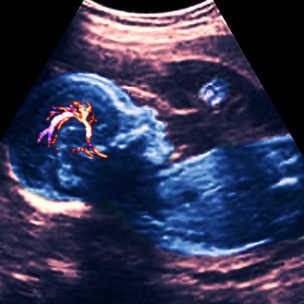

一种常见的先天血管缺陷是脑动静脉血管畸形(anarteriovenous malformation 简称AVM)。

专家称,这种在胚胎期形成的缺陷会使动脉血在不经过毛细血管的情况下直接注入静脉,并可能在高速高压注入时形成血液短路,并最终导致脑出血和中风。